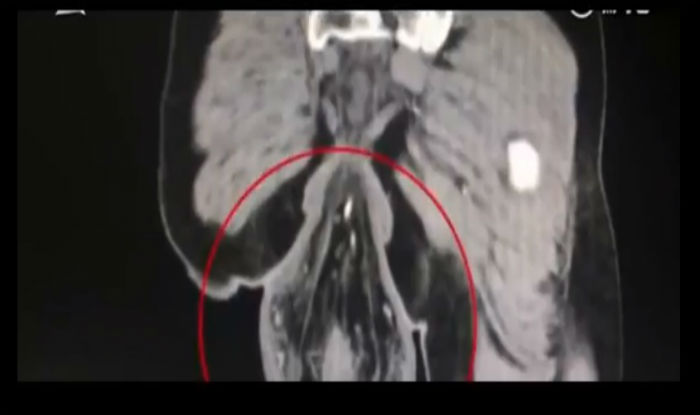

Hình quang tuyến cho thấy phần trĩ lòi ra ngoài hậu môn.

Các bác sĩ đã tìm thấy một cái “đuôi” dài chừng 16 cm lòi ra khỏi hậu môn của ông, và chẩn đoán ông bị trĩ trực tràng, theo bản tin cho biết. Bản tin nói thêm rằng ông đã chơi quá lâu với điện thoại di động trong khi đi vệ sinh.